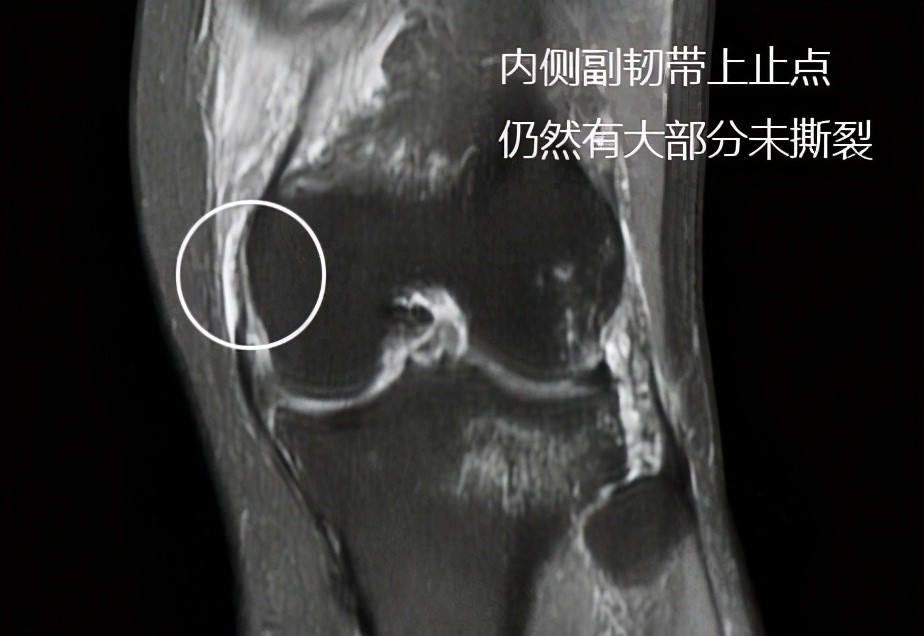

发生了较大撕裂,但是在核磁上我们发现内侧副韧带损伤相对来讲不是特